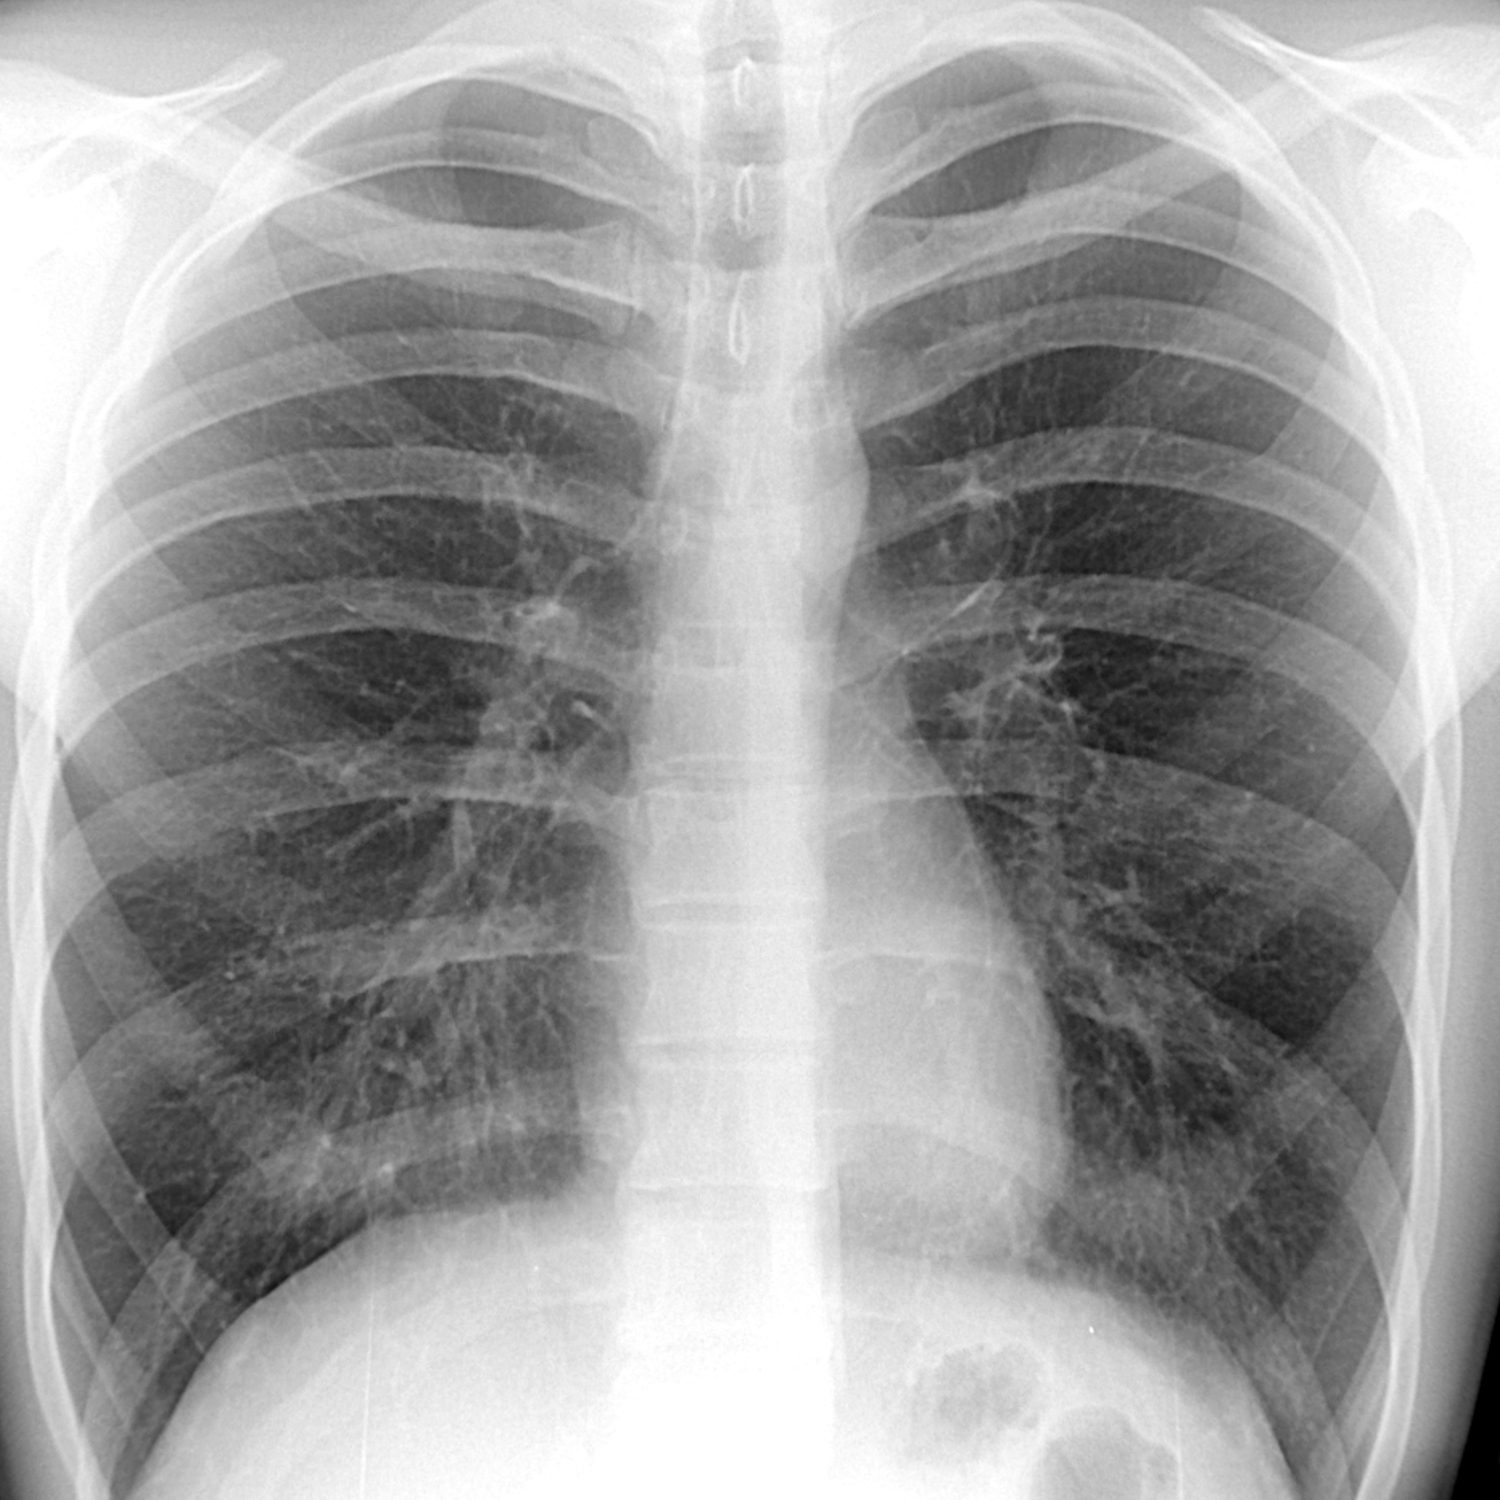

Нормальная рентгенограмма легких: что нужно знать

Раздел: Мудрость в объективе